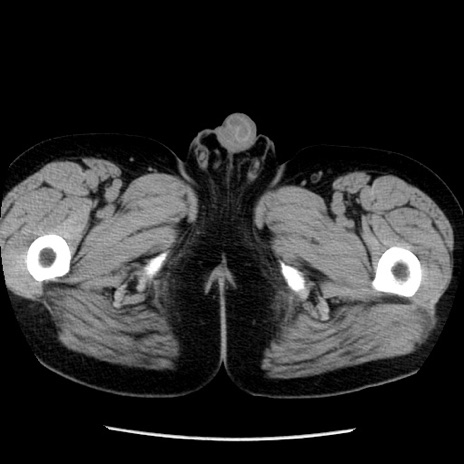

症例29(横断像)

【症例】40歳代男性

【現病歴】2日前から胃痛あり。徐々に周期的な激痛に変化した。本日になっても激痛があるため受診。

【身体所見】意識清明、BT 38-39℃台あり、腹部:膨満、やや硬、右下腹部に圧痛あり。

【データ】WBC 8500、CRP 23.26